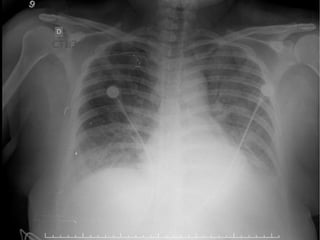

Orientada, corada, hidratada, acianótica, taquipnéica, afebril

AR: MV diminuido, crepitações difusas bilaterais ; Sat – 98% ; FR =

30irpm ; O2 por tenda facial a 4l/min

Observa-se derrame pleural bilateral maior a esquerda